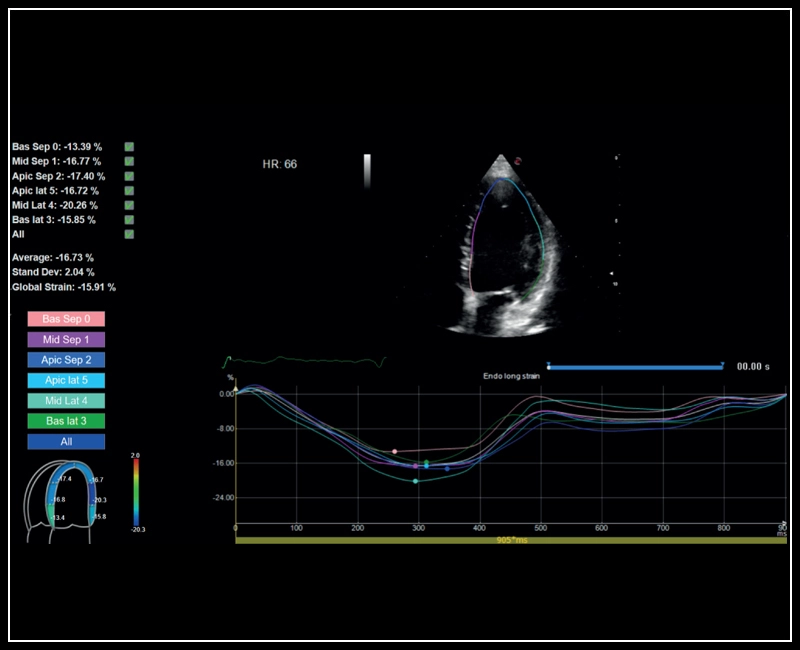

MyLab™Sigma - Left Ventricle XStrain 2D analysis

MyLab™Sigma - Left Ventricle XStrain 2D analysis

MyLab™X90 - XStrain™ LV Automatic assessment of global longitudinal strain in the left ventricle

MyLab™X90 - XStrain™ LV Automatic assessment of global longitudinal strain in the left ventricle